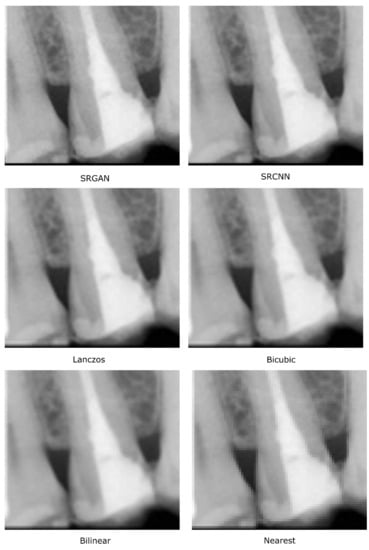

These visual quality differences are exemplified in Figure 7, in which it is possible to see how the deep-learning methods increase the edges’ definition in the interproximal area.

Figure 7.

Details (of two interproximal areas) in images obtained by the considered methods.